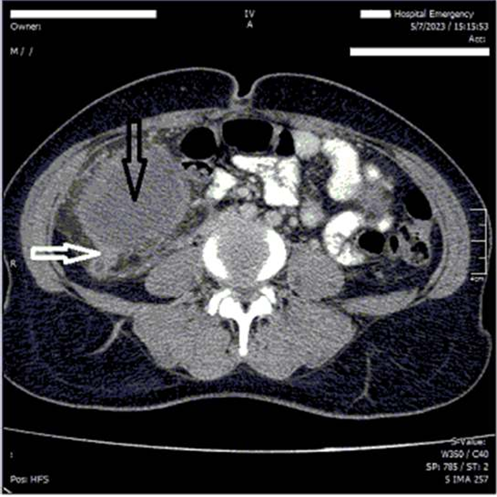

A 40 years old woman was admitted to our emergency department (Ghaem Hospital, Mashhad) with abdominal pain for three days ago. She had a medical history of two cesarean sections in 7 and 5 years ago. She reported abdominal pain in the upper abdomen, which then shifted to the right lower quadrant. She experienced one episode of fever, anorexia, nausea, and vomiting. Physical examination revealed a fullness and mass-like lesion in the lower abdomen, with tenderness and rebound tenderness in the right lower quadrant. She had leukocytosis (WBC 17000) and elevated C-reactive protein levels. Acute appendicitis with phlegmon has been reported on abdominal ultra sonography. Computed Tomography (CT) the abdomen and pelvis revealed acute appendicitis with two huge intra- abdominal foreign bodies (Figure 1). The patient underwent midline laparotomy, intra-operative finding included; two huge intra-abdominal masses in lower abdomen with severe inflammation and adhesion of the appendix and also adhesion of the right fallopian tube and ovary to the right mass (Figure 2). The abdominal masses, appendix, right fallopian tube and right ovary were excised (Figure 3). Gross pathologic findings of both abdominal masses were contained surgical gauzes; the right mass was full of pus with invasion and perforation of the appendix tip by gauze (Figure 4). Acute suppurative appendicitis was confirmed by a permanent pathologic report.

Figure 1C. Appendix with severe inflammation and adhesion to the mass (White arrow) Right huge abdominal mass (Black arrow).

Figure 2. Appendix with severe inflammation and adhesion to the mass (Black arrow) Right huge abdominal mass (White arrow).